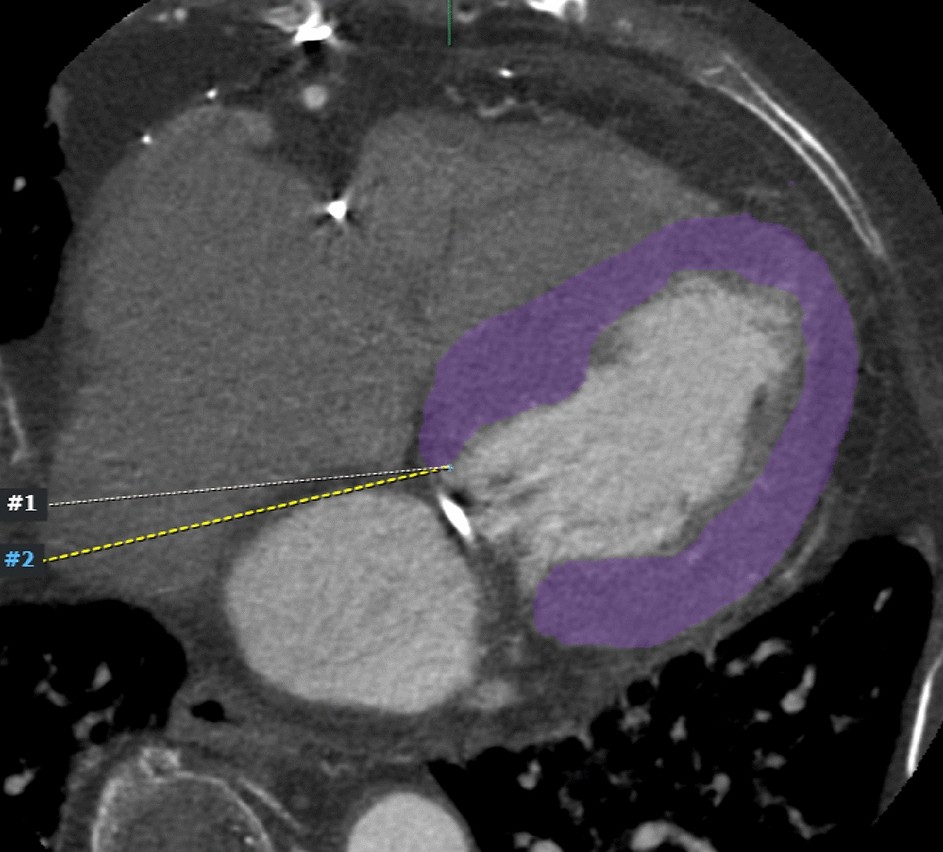

Figure 4

Axial cardiac CT image of a 77-year-old female patient. The myocardium (purple color) is segmented by excluding the LV blood pool and trabeculae to improve reproducibility for delineating the endocardial border. CT, computed tomography; LV, left ventricular.